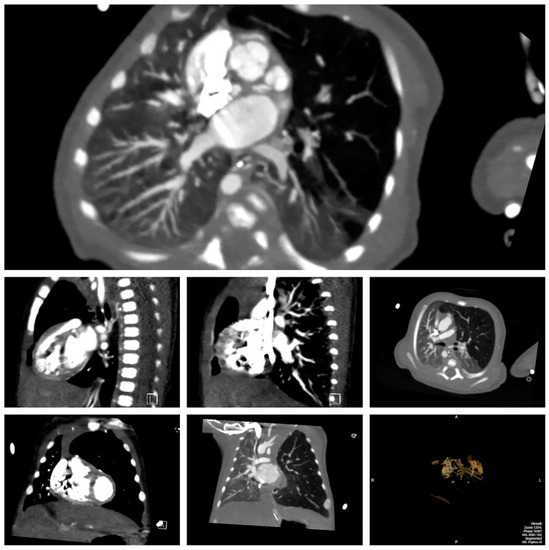

Figure 3.

Multiple views on cardiac computed tomography (CT) demonstrating tertiary tracheal bronchus supplying the lingula with stenosis at the origin, double outlet right ventricle (DORV) with transposition of the great vessels, hyperinflated left upper lobe, partially atelectatic left upper and lower lobes, herniation to the right, and 3D reconstruction of airway.